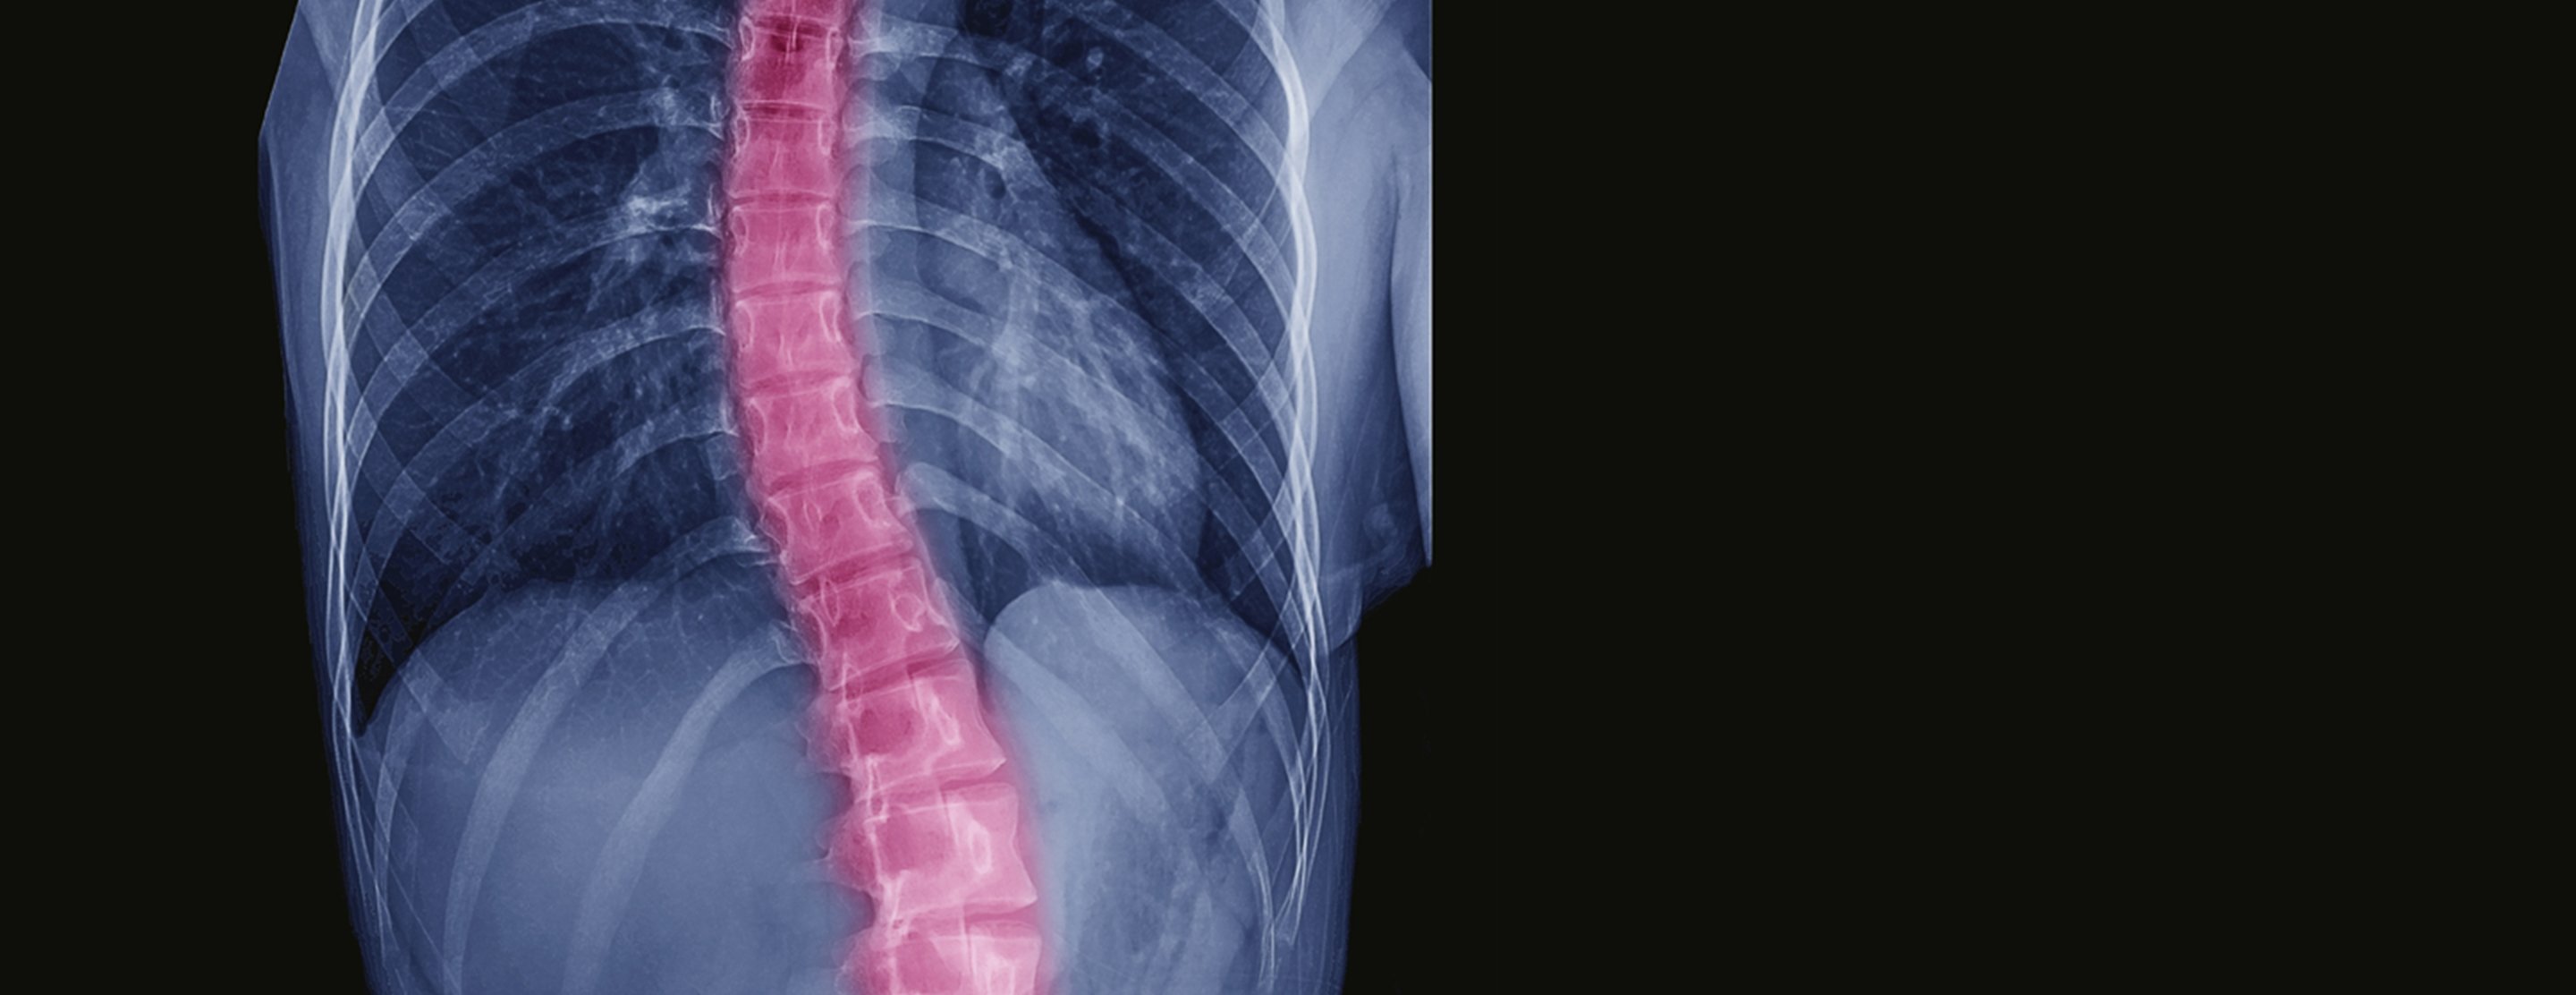

The goal of spinal surgery for scoliosis is to fuse the vertebrae so the spine cannot bend and to correct deformity. The doctor will try to correct the curve by 50 percent or more.

An incision is made in the middle of the back. The muscles are moved to the side to expose the spine. The joints between the vertebrae are removed to loosen them up. The vertebrae are roughened up so that the body responds by producing new bone. The new bone eventually bridges the gaps between the vertebrae and makes them fuse together. Metal implants – rods, screws, hooks or wires – are put in to hold the spine still while the vertebrae fuse.